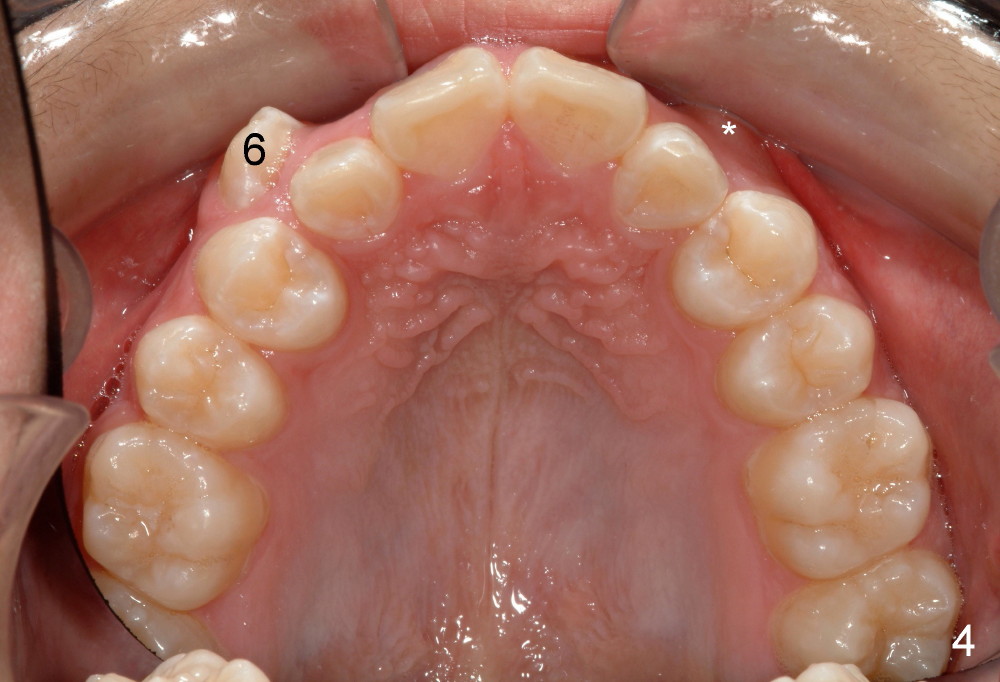

Tim: Thank you so much for the tip.  It appears that an alastik is placed between #6 bracket and the upper AW.  Can you recommend surgical exposure of #11?

We are teasing tooth #6 down initially with a light elastic force. This will minimize any reciprocal forces on the anterior teeth. I do not want to intrude the incisors while extruding 6. That would potentially open the bite.

You will see tooth #11 continue to erupt spontaneously. In the initial photos, it was not visible. It was simply mechanically blocked out. And the tissue will b the best when the tooth erupts spontaneously. Bet on 11 to erupt😉 and a couple more mm of eruption and I will b able to place a button and like 6, begin to tease down faster.